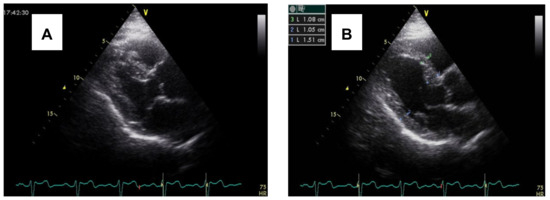

3.2. Imaging and Hemodynamic Observations

- Çağatay, B.; Yalçin, F.; Kıraç, A.; Küçükler, N.; Abraham, M.R. The Science Behind Stress: From Theory to Clinic, Is Basal Septal Hypertrophy the Missing Link between Hypertension and Takotsubo Cardiomyopathy? Stresses 2024, 4, 330–341. [Google Scholar] [CrossRef]

- Yalçin, F.; Topaloglu, C.; Kuçukler, N.; Ofgeli, M.; Abraham, T.P. Could Early Septal Involvement in the Remodeling Process Be Related to the Advance Hypertensive Heart Disease? IJC Heart Vasc. 2015, 7, 141–145. [Google Scholar] [CrossRef]

- Yalçin, F.; Yalçin, H.; Seyfeli, E.; Akgul, F. Stress-Induced Hypercontractility in Patients with Hypertension: An Interesting Imaging Finding. Int. J. Cardiol. 2010, 143, e1–e3. [Google Scholar] [CrossRef]

- Yalçin, F.; Çağatay, B.; Küçükler, N.; Abraham, T.P. Geomeric and Functional Aspects in Hypertension and Takotsubo: Importance of Basal Septal Hypertrophy. Eur. J. Prev. Cardiol. 2023, 30, 1996–1997. [Google Scholar] [CrossRef]

- Yalçin, F.; Muderrisoǧlu, H. Tako-Tsubo Cardiomyopathy May Be Associated with Cardiac Geometric Features as Observed in Hypertensive Heart Disease. Int. J. Cardiol. 2009, 135, 251–252. [Google Scholar] [CrossRef]